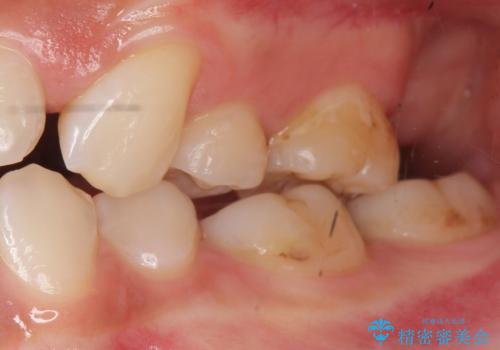

- 奥歯が黒くなっていることを気にされ来院された患者様です。

精査したところ、左下の奥歯にう蝕を認めました。

患者様のご希望により、う蝕を丁寧に除去したのちセラミッククラウンによる補綴治療を行いました。